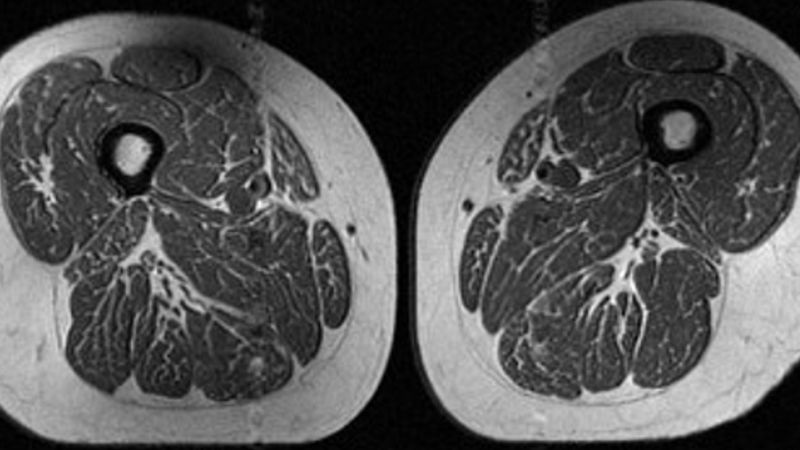

The image looks like a slice of highly marbled flesh, reminiscent of a high-end steak with abundant fine-grained streaks of fat. But that’s not dinner. It’s an MRI scan of the thigh of a 62-year-old woman…